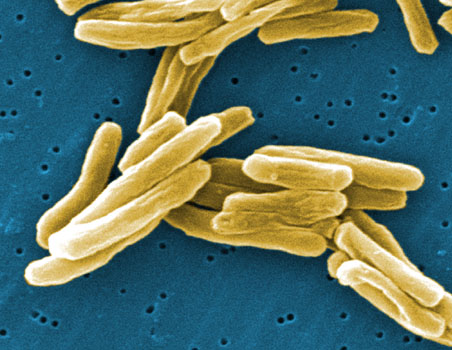

New avenues in fight against drug resistant TB

While rising drug resistance in Mycobacterium tuberculosis is eroding the power of almost all available antibiotics in the fight against this major pathogen, work completed by MWC-

The MWC has long recognised the value in investing in research to fight infectious diseases such as tuberculosis (TB), which remains difficult to treat or prevent. MWC teams are co

High-impact publications highlight TB research

Researchers in the MWC’s Tuberculosis Flagship Research Programme have had their long hours in the lab recognised through publications in world-leading journals.

An estimated 1.3 million people die from tuberculosis (TB) each year, and new drugs are desperately needed, especially as resistance to existing drugs increases.

Stepping up the fight: The Tuberculosis Flagship (2013)

The Maurice Wilkins Centre is behind the launch of a national research network of ‘serious intellectual muscle’ that aims to speed up action against tuberculosis.

New inhibitor for tuberculosis (2011)

A new way to shut down the bacterium responsible for tuberculosis has been devised by researchers in one of the Maurice Wilkins Centre’s longest-standing collaborations.

Modern approaches to an ancient disease (2010)

Scientists associated with the Maurice Wilkins Centre have created new drugs for tuberculosis.